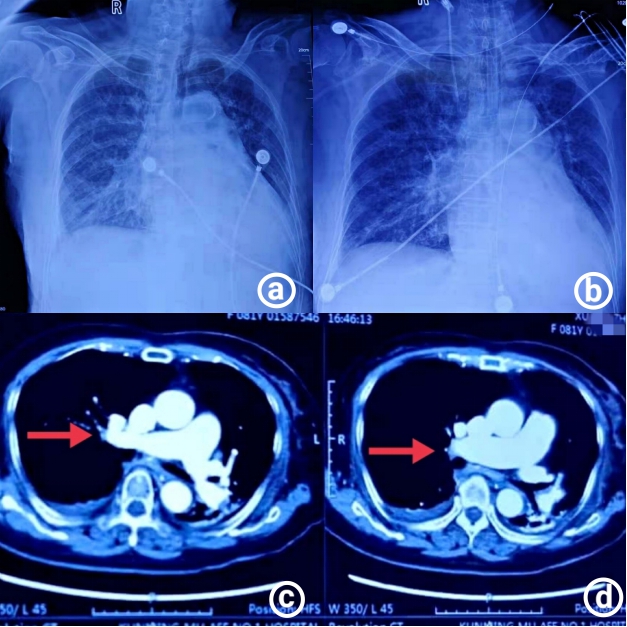

1.4 诊治经过及临床转归入院诊断:急性胃肠炎。给予“拉氧头孢2 g q12 h静脉滴注”抗感染,冠心病二级预防,控制血压,控制心室率,补液,维持电解质平衡等对症治疗,2020年12月1日19:00患者出现胸闷、喘息、呼吸困难、烦躁,血气分析:pH 7.39,PO2 78 mmHg,PCO2 19 mmHg,乳酸4.7 mmol/L,氧合指数128 mmHg,面罩给氧,氧流量10 L/min,白细胞33×109/L,中性粒细胞百分比88.50%,血红蛋白69 g/L,降钙素原6.73 ng/mL,超敏C反应蛋白 > 200 mg/L;胸片提示双肺多发渗出病灶(图 1A),给予高流量吸氧,流量50 L/min,FiO2 90%,呼吸科会诊指导对症处理。2020年12月2日肌红蛋白165.36 μ g/L,肌钙蛋白Ⅰ 19.567 ng/L,B型钠尿钛 > 4 500 pg/mL;患者肌钙蛋白Ⅰ和心衰指标明显升高,呼吸困难明显,口唇发绀,出现谵妄症状,不排除急性冠脉综合征可能,请心内科、ICU会诊后,随即转入ICU,血气分析:pH 7.15,PO2 103 mmHg,PCO2 27 mmHg,BE -17.9 mmol/L,HCO3- 11 mmol/L,乳酸8.4 mmol/L,氧合指数103 mmHg。患者氧饱和度进行性下降,呼吸骤停,立即给予气管插管呼吸机辅助呼吸,2~3 h内患者先后出现4次心搏骤停,间断心肺复苏成功后,立即复查心电图示快速房颤,T波改变,复查心肌酶学及感染相关蛋白,呼吸、心率、氧合稳定后,用转运呼吸机将患者快速转至心导管室急诊行PCI,提示:左前降支狭窄30%~40%,右冠狭窄20%~30%,排除急性心肌梗死;床旁心脏超声提示:右室、左房和升主动脉内径扩大,肺动脉收缩压增高,左室舒缩功能减弱;患者体温39℃,立即行血培养、床旁纤支镜检查取深部痰液行痰培养,同时送血、肺泡灌洗液进行病原宏基因组学检测。

| 图 1 患者影像学结果(A:患者入院胸部X线,双肺多发渗出病灶;B:治疗后胸部X线,肺部炎症渗出好转;C、D:患者胸部CTA结果,箭头所指处为右肺下叶前基底段动脉局部可疑充盈缺损影,肺栓可能) |

综合征状、体征及检验结果考虑患者为:急性胃肠道感染、脓毒性休克、多器官功能障碍综合征、急性肺栓塞可能,立即予“亚胺培南西司他丁钠1 g q6 h联合万古霉素0.5 g q12 h”抗感染,呼吸循环支持,去甲肾上腺素应用,补液,低分子肝素抗凝,同时兼顾心功能,纠正贫血,人血白蛋白、呋塞米应用,免疫球蛋白冲击20 g/d,改善免疫功能,共用5 d,保护重要脏器功能,纠正内环境紊乱等对症治疗。根据血药浓度及肝肾功能调整抗生素剂量,但患者仍有间断发热,三次血痰培养均为阴性。2020年12月5日血液宏基因组学检查报告为阴性,肺泡灌洗液宏基因组学检查报告提示“TW”,调整抗生素为头孢哌酮舒巴坦钠3 g q8 h、氟康唑400 mg qd、复方磺胺甲恶唑片2片q12 h协同抗感染治疗。2020年12月6日行胸部血管CTA检查提示:右肺下叶前基底段动脉局部可疑充盈缺损影,肺栓塞可能,继续予低分子肝素抗凝治疗(图 1C、D)。2020年12月7日床边胸片提示肺部炎症渗出好转(图 1B),但患者仍存在循环不稳定,阵发性房颤,需大剂量去甲肾上腺素维持血压,予强心(去乙酰毛地黄苷及左西孟旦)、利尿治疗,心功能改善,循环趋于稳定;经针对性抗感染治疗后患者白介素6、降钙素原、C反应蛋白指标下降,淋巴亚群免疫指标恢复正常。患者于2020年12月9日拔除气管导管,予无创呼吸机与高流量辅助通气交替应用,逐渐过渡为面罩给氧,但患者出现心率升高伴有谵妄表现,心率波动于130~150次/min,为窦性心动过速伴有频发室早,再次评估病情后,加强排痰,纠正贫血、予艾司洛尔、美托洛尔及伊伐布雷定控制心室率,左西孟旦、辅酶Q10改善心功能[3],睡前口服阿普唑仑联合奥氮平改善睡眠、抗焦虑、谵妄治疗后,病情逐渐好转。2020年12月11日复查肺泡灌洗液宏基因组学未再检测出TW;2020年12月14日复查胸部CT示双肺片状磨玻璃影及实变影较前吸收,双侧胸腔积液较前吸收,逐渐停用抗生素,更换低分子肝素为利伐沙班口服抗凝治疗。经过21 d治疗,患者于2020年12月20日治愈出院,出院时感染指标恢复正常,肝、肾功能正常,三大常规均无异常。